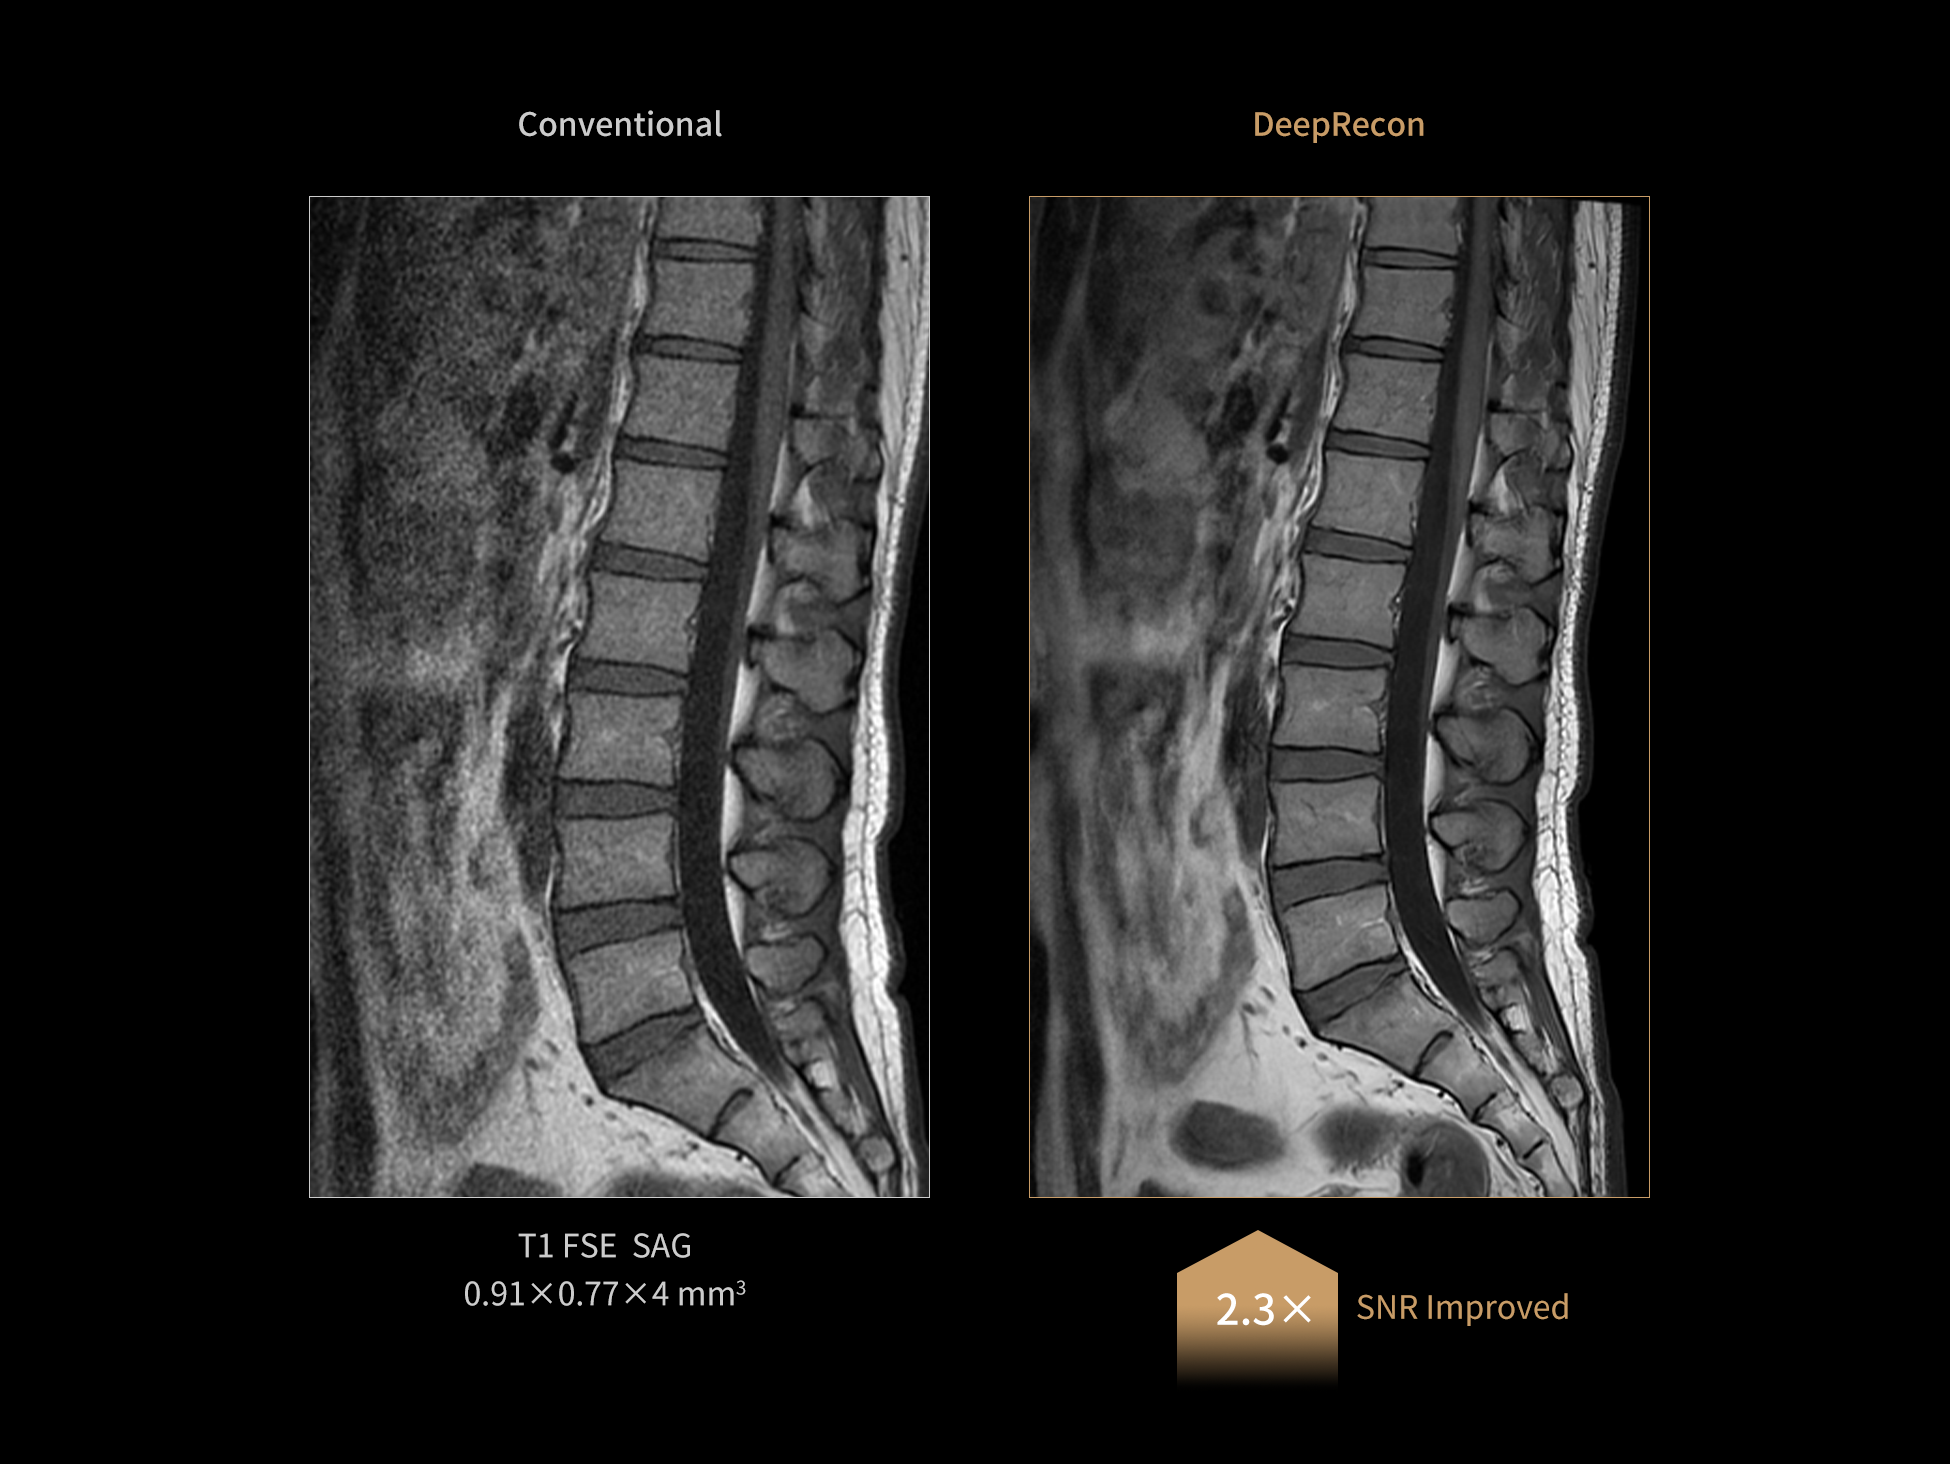

Using the same protocol, DeepRecon is capable of significantly enhancing the signal-to-noise ratio (SNR) and providing rich image details.

Images courtesy of United Imaging.